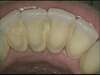

DÉTARTRAGE